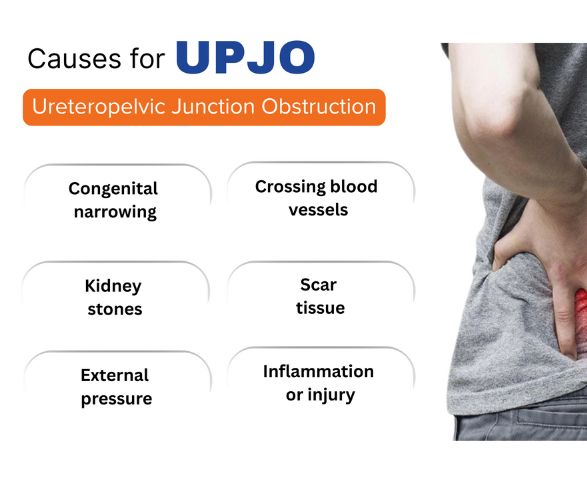

Causes of UPJ Obstruction

UPJ obstruction occurs when a blockage at the ureteropelvic junction prevents urine from flowing normally from the kidney to the ureter. This leads to urine buildup in the kidney (hydronephrosis) and may affect kidney function over time. The main causes include:

Congenital narrowing – Many cases are present from birth due to abnormal development of the ureter.

Crossing blood vessels – Nearby blood vessels may compress the ureter, causing obstruction.

Scar tissue or strictures – Inflammation, previous surgery, or injury can lead to narrowing at the junction.

Kidney stones – Stones can block or irritate the UPJ, leading to obstruction.

Infections or inflammation – Recurrent urinary infections may cause swelling and scarring.

Previous procedures or trauma – Surgical interventions or injury to the kidney or ureter may result in obstruction.